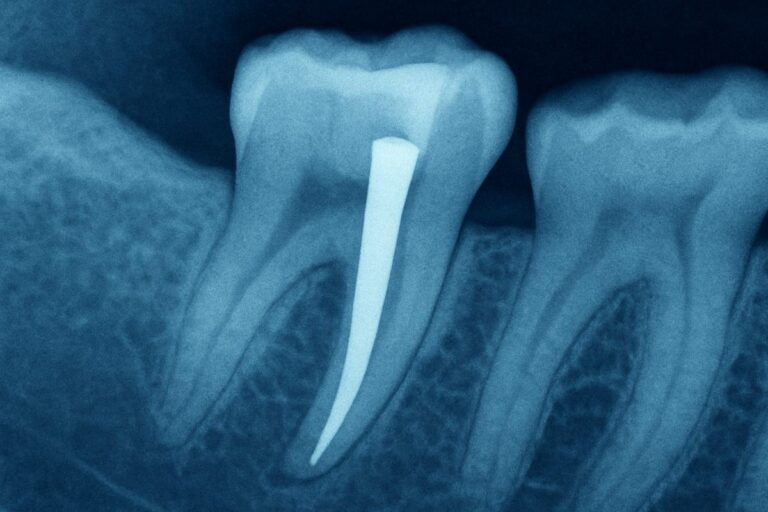

A tooth with post is a common way dentists near Lake St. Louis, MO save a badly broken or root-canal-treated tooth. If you live near